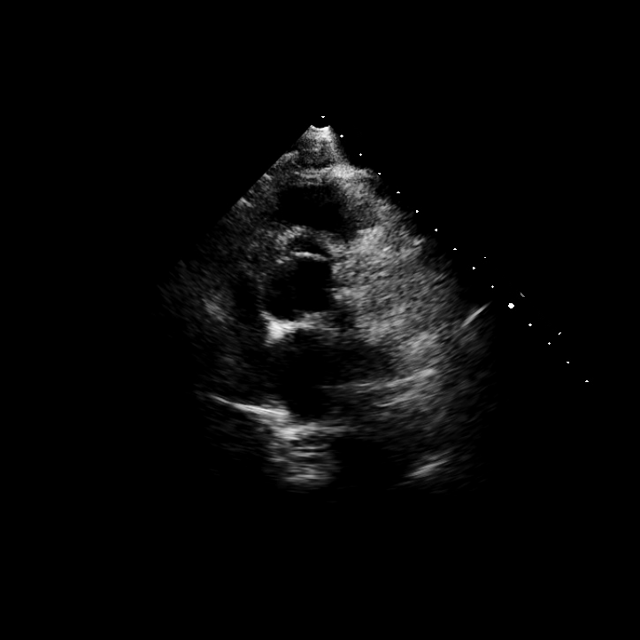

2.4 Landmark Detection for Left Ventricle Measurements

Left ventricular hypertrophy (LVH) is an adaptation of the cardiac muscle in response to disease, cardiac wall stress or significant hemodynamic pressure. Its diagnosis is crucial as patients with LVH are at increased risk of developing heart failure, arrhythmia, strokes and sudden death [Drazner2011ThePO]. Left ventricular wall measurements using echocardiography in the parasternal long-axis (PLAX) view are widely used in the diagnosis of LVH. However these measurements are subject to inter-observer and intra-observer variability due to the complexity of the myocardial shape, imaging artefacts and image quality [Phelan2017ComparisonOV].

In clinical practice, the LV mass is indexed against the body surface area to and compared to reference values to perform a diagnosis of LVH and determine its severity [Barbieri2012LeftVH]. Three key measurements are taken in the PLAX view to compute the LV mass: The intraventricular septum (IVS), the LV internal dimension (LVID) and the LV posterior wall thickness (LVPW). AI-driven approaches in medical imaging have demonstrated significant potential in enhancing the accuracy and consistency of cardiac measurements. AI models can analyze echocardiographic images with a high degree of precision, minimizing human error and subjectivity and thus benefiting the clinical workflows [Howard2021AutomatedLV, Augusto2020DiagnosisAR].

2.4.1 Supervised landmark detection for left ventricle wall thickness measurements

We use our pre-trained EchoApex model as an image encoder and a decoder architecture inspired by UNETR [hatamizadeh2022unetr], as described in Fig. 5(a). We compare our model with the state-of-the-art method from [Duffy2021HighThroughputPP] which uses a DeepLabV3 [Chen2017RethinkingAC] backbone, retrained following the authors’ specifications. All hyperparameters are listed in the Supplementary Table. 10. Training is conducted on the training split of the EchoNet-LVH dataset [Duffy2021HighThroughputPP] while testing is performed on two datasets: the test split of EchoNet-LVH (internal dataset) and the validation split of the Unity dataset [Howard2021AutomatedLV] (external dataset). Fig. 5(b) details the distribution of the measurements for the two datasets.

We report the average landmark error (L2 norm) between all landmarks and the Mean Absolute Error (MAE) on the three key measurements on the internal EchoNet-LVH (resp. Fig. 5(c) and Fig. 5(e)) and external Unity test datasets (resp. Fig. 5(d) and Fig. 5(f)). Qualitative results showing attention maps and landmark predictions are shown in Fig. 5(g) and in the Supplementary Fig. 9.